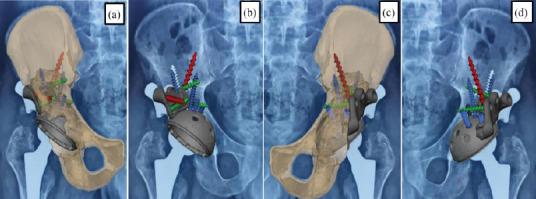

This retrospective case series includes seven patients who underwent revision THA for Paprosky grade 3 acetabular bone loss between January 2023 and April 2024 at two high-volume tertiary care centers. The mean age of the patients was 45 years, with three males and four females included in the study. Pre-operative planning involved advanced imaging techniques, including 3D-computed tomography scans and custom virtual modeling, to design the acetabular components tailored to each patient's specific anatomical requirements.During the surgeries, custom-made 3D-printed titanium augments and cages were used. These implants were fabricated using in-house software, and the turnaround time from the decision to surgery was approximately 10 days. Post-operatively, the planned 3D model was superimposed on post-operative radiographs to assess implant placement accuracy. The Harris hip score at the final follow-up averaged 69.16, with no signs of implant loosening observed.

本回顾性病例系列包括7例患者,他们于2023年1月至2024年4月在两家大型三级医疗中心接受了因Paprosky 3级髋臼骨丢失而进行的翻修全髋关节置换术。患者的平均年龄为45岁,研究纳入了3名男性和4名女性。术前规划涉及先进的成像技术,包括3D计算机断层扫描和定制虚拟建模,以设计适合每个患者特定解剖需求的髋臼组件。在手术过程中,使用了定制的3D打印钛增强物和笼。这些植入物使用内部软件制造,从决定手术到手术的周转时间约为10天。术后,将计划的3D模型叠加在术后X线片上以评估植入物放置的准确性。最后一次随访时的Harris髋关节评分平均为69.16,未观察到植入物松动的迹象。